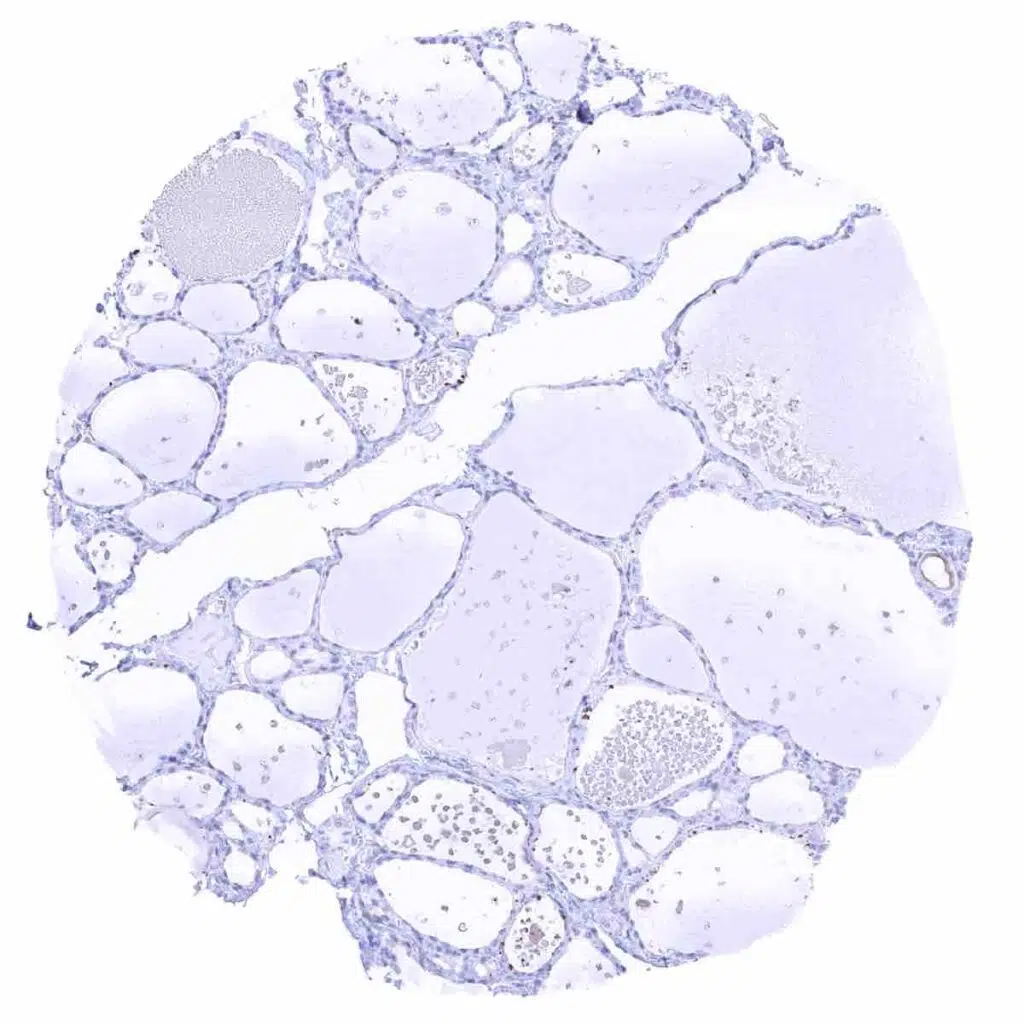

Thyroid gland